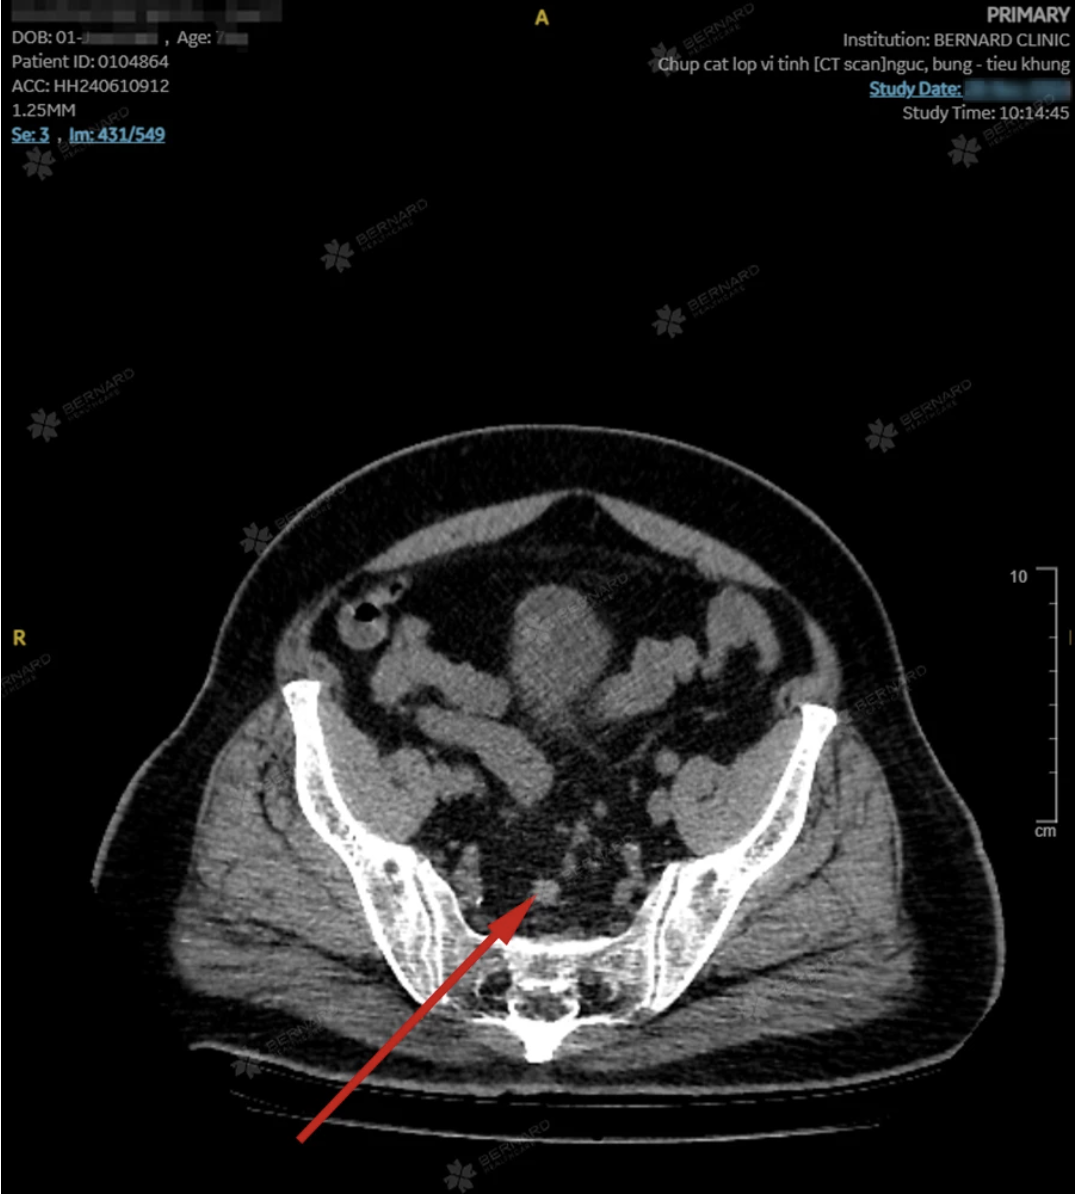

Chụp CT sau đó ghi nhận tổn thương lan rộng, dày thành trực tràng và có hạch quanh khu vực. Nhận định đây là ca bệnh tiến triển, các bác sĩ Bernard đã lập tức hội chẩn liên chuyên khoa Nội - Ngoại - Chẩn đoán hình ảnh và chuyển bệnh nhân đến bệnh viện chuyên khoa ung bướu để tiếp tục điều trị.